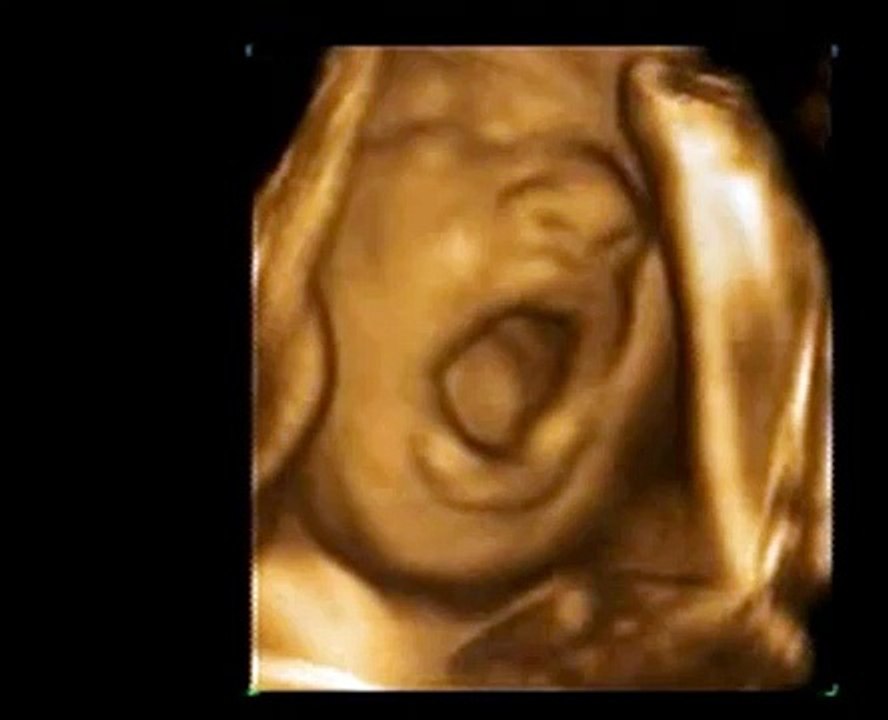

3d Ultrasound 30 Weeks Yawning Baby A New Conception 3d Video Dailymotion